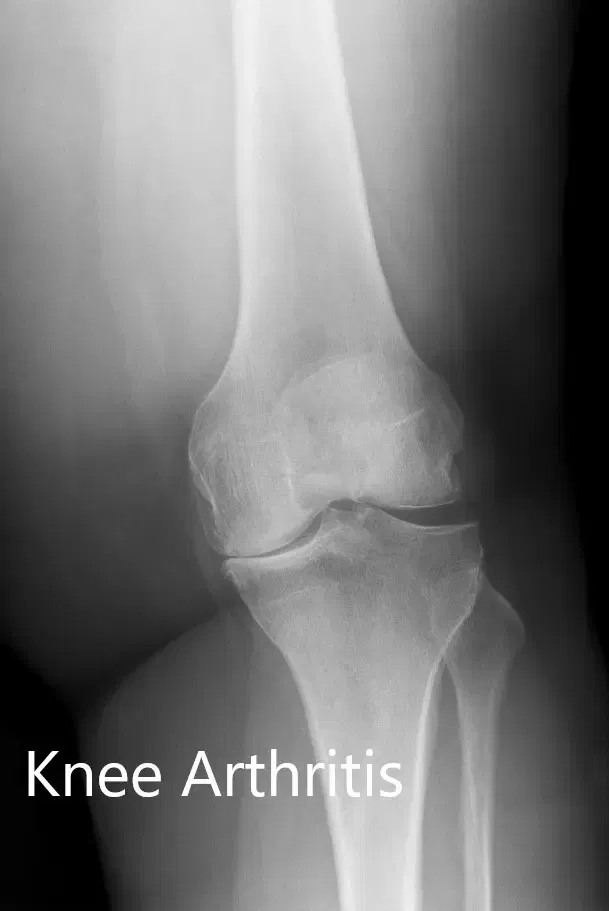

No hubo déficit neurológico distal y los pulsos distales bilaterales fueron comparables. Los reflejos bilaterales de los tendones superficiales y profundos de la extremidad inferior fueron positivos y comparables. Las imágenes revelaron osteoartritis en las rodillas bilaterales (izquierda > derecha). Se impartió educación sobre dejar de fumar al paciente.

Radiografía preoperatoria que muestra la visión AP y lateral de la rodilla izquierda